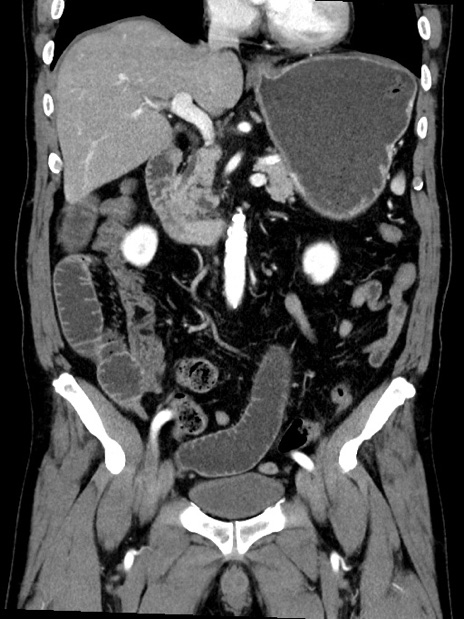

症例35(冠状断像)

【症例】70歳代 男性

【主訴】腹部膨満、嘔吐

【現病歴】昨日より腹部膨満感出現。本日増悪し、仙痛出現。嘔吐あり、受診。

【既往歴】糖尿病、胆摘後

【身体所見】BP 149/80mmHg、HR 74/min、BT 35.9℃、腹部:膨満、軟、圧痛なし。腸雑音減弱あり。上腹部正中切開瘢痕あり。

【データ】WBC 13500、CRP 1.72